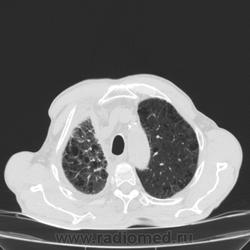

Пожилой мужчина, лечился по н/д правостороннней пневмонии в терап/отделении. Жалобы на одышку, кашель. По результатам Р-контроля после лечения направлен на КТ легких с диагнозом: плеврит справа, распад? В корне правого легкого вижу объёмное образование, с распадом. Смущают размеры плеврита,очень много жидкости, почти до 3 ребра. Анализы крови спокойные- L4,0-6,6, СОЭ 12-16мм. Неужто ТБС, отсев бы был при таком огромном поражении. В посеве мокроты-100% высев клебсиэллы пневмоние. Мокрота на общий анализ в работе-собирает с трудом, изза отсутствия мокроты. Плевральную пункцию еще не проводили. Н азначила бронхоскопию и плеврал пункцию. Как думаете, уважаемые коллеги, это онкопроцесс или тбс распад?

Самое интересное забыла показать- может это 100% навеет на мысль об опухолевом процессе, остеолитическая деструкция позвонка?

Не смотря дайкомы, только по рентгенограмме, предположил бы центральный рак правого легкого. Потому что большой гидроторакс, без смещения средостения в здоровую сторону, как правило, соответствует раковому ателектазу.

Коллеги, распада там нет, это вас медиастинальное окно подвело. В грудине тоже все в порядке. Да и компрессия позвонка "старая".

Небольшое количество увеличенных лимфоузлов, и те - не сказать, чтоб были очень крупными. От эмпиемы до онкологии... Умеренное количество жидкости в перикарде, толщиной слоя до 13-14 мм. При подобной картине не вижу смысла гадать по сжатому лёгкому, пишу так: массивный выпот справа, около 2500 мл, диафрагма оттеснена жидкостью каудально, печень (!!!) смещена каудально и вправо. Легкое справа значительно компрессировано жидкостью, оценка проходимости бронхов и состояния легочной паренхимы (кроме имеющейся эмфиземы) практически невозможна. Необходима пункция плевральной полости справа (цитология, ВК, посев на микрофлору и проч), КТ-контроль после эвакуации жидкости.